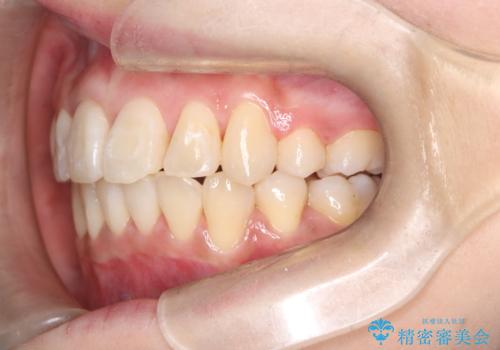

八重歯と正中のズレを解消!目立ちにくいワイヤー矯正で美しい歯並びへ

- 八重歯(叢生)と、上下の歯の中心線(正中)がずれていることを主訴にご来院されました。精密な検査の結果、歯列全体のスペースが大幅に不足しており、八重歯を正しい位置に配列し、正中のズレを改善するためには、上下左右の第一小臼歯を抜歯する必要があると診断。装置には、目立ちにくい審美ワイヤーを使用し、見た目を気にせず、機能性と審美性が完璧に整った咬み合わせを目指す治療計画を立案しました。

今回の矯正治療では、まず計画通り上下左右の小臼歯4本を抜歯し、八重歯や正中のズレを解消するための十分なスペースを確保しました。装置には、目立ちにくい白いブラケットとワイヤーを使用した審美ワイヤー矯正を採用。

八重歯: 突出していた八重歯を歯列内に誘導し、デコボコを解消しました。

正中のズレ: 歯を左右対称に移動させることで、上下の歯の中心線を正確に合わせ、顔全体のバランスも改善しました。

治療の結果、長年気にされていた八重歯と正中のズレが解消し、機能的にも整った理想的な歯並びを獲得。目立たない装置で治療を完遂し、自信を持って笑える美しい笑顔を手に入れていただけました。